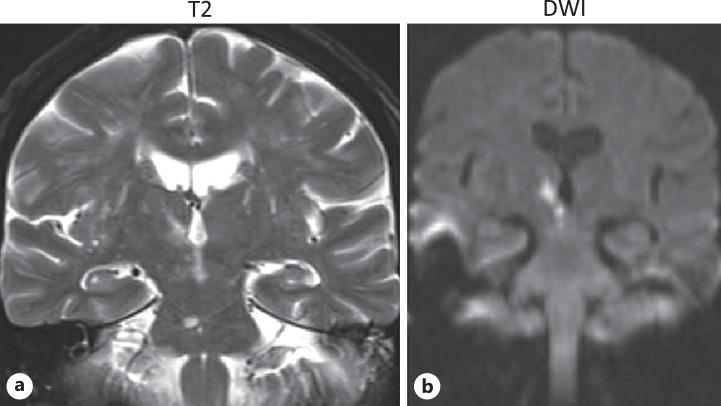

We report a patient presenting with unique neuroophthalmological features of contraversive ocular tilt reaction and concomitant contralesional pseudo-abducens palsy. Magnetic resonance imaging confirmed the presence of an acute infarct in the right thalamomesencephalic region. We discuss the clinical topography of these unique neuroophthalmological findings.

我们报告了一名患者,其表现出反向性眼倾斜反应及同侧假性展神经麻痹的独特神经眼科特征。磁共振成像证实右侧丘脑-中脑区域存在急性梗死。我们讨论了这些独特神经眼科表现的临床定位。